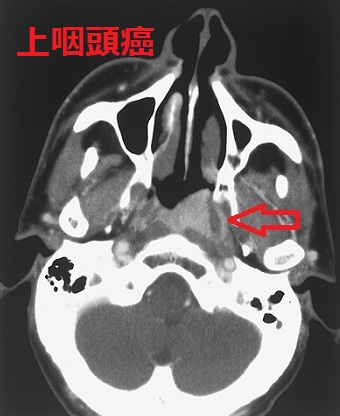

若年性血管線維腫は放射線治療が行われ放射線誘発性甲状腺がんの問題があった。喉頭乳頭腫はヒトパピローマウイルス(HPV)感染が原因の良性腫瘍だが稀に癌化。甲状腺乳頭癌の副咽頭間隙転移、下咽頭転移はまれ。喉頭癌・下咽頭癌(扁平上皮癌)の甲状腺転移がある。上咽頭扁平上皮がんはヘルペスウイルスの一種、EBウイルス(エプスタイン・バールウイルス)が主な原因。未分化扁平上皮がんが多く、放射線感受性が高いため放射線根治治療になり、放射線甲状腺炎や放射線唾液腺炎の合併症・後遺症が生じる。

若年性血管線維腫,甲状腺がん,甲状腺乳頭癌,上咽頭がん,転移,喉頭癌,下咽頭癌,扁平上皮癌,甲状腺転移,甲状腺